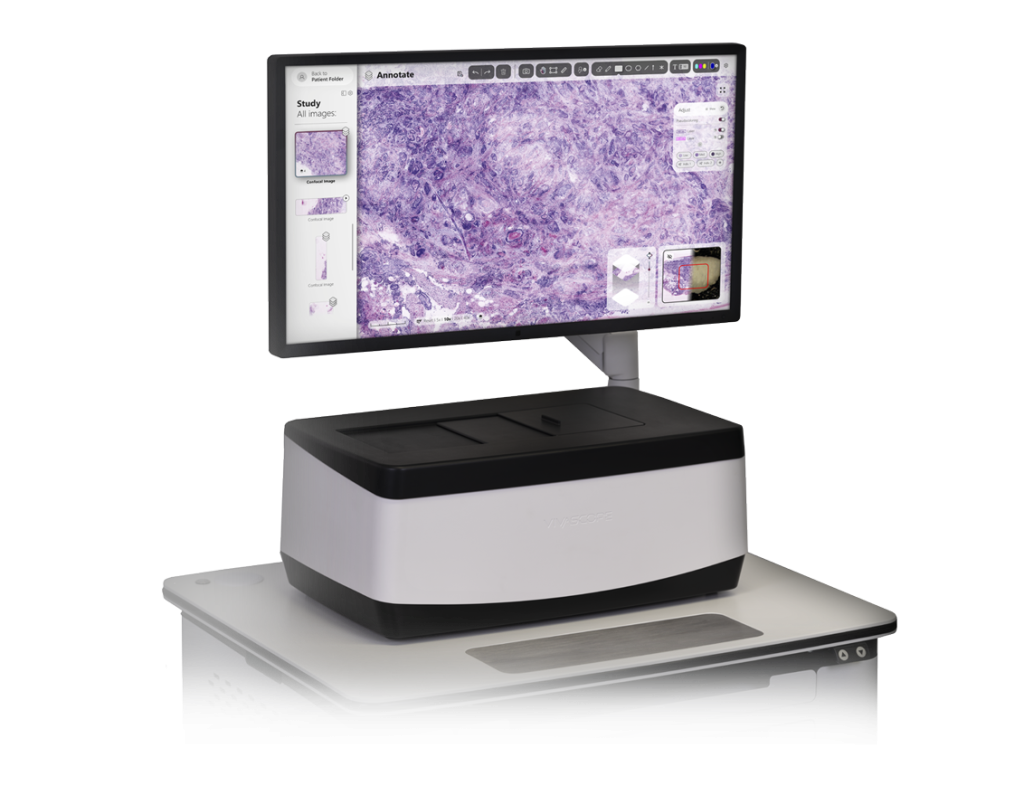

The VivaScope 2500 Ex Vivo technology offers H&E-like images, generated from two components. Two lasers of different wavelengths create two distinct images, a fluorescence image and a reflectance image. Both signals are scanned simultaneously and are used to create pseudo-colored images. The device’s software uses an algorithm to translate the acquired image information into colors that resemble H&E.

The VivaScope 2500 rapidly scans the excised tissue and reveals the cellular morphology right at the bedside. The examined tissue remains unharmed by the procedure and can be preserved for later histopathological analysis.

High resolution images of unfixed tissue without sectioning. Within 5 minutes, digital and on the bedside. The device’s software uses an algorithm to translate the acquired image information into colors that resemble H&E.